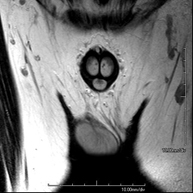

- RM Pelvis masculina

Prueba diagnóstica no invasiva que consiste en la obtención de imágenes de alta definición anatómica de la pelvis masculina mediante el empleo de un campo electromagnético y ondas de radio (con un emisor y un receptor). No utiliza radiación ionizante. No requiere de preparación previa. En algunas ocasiones requiere el empleo de contraste paramagnético (Gadolinio) para caracterizar las lesiones. Esta prueba permite valorar órganos como la vejiga urinaria, la unión entre los uréteres y la vejiga, la próstata, las vesículas seminales, la uretra, los huesos de la pelvis, etc.